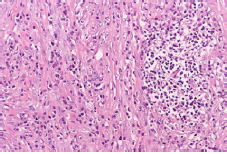

Then, histological cutting was performed (Figure 8) and taken to a laboratory where proliferation of spindle cells (which surround the vessels) and abundant inflammatory infiltrate were identified.

Microscopy of the tumor segment in sectioned terminal ileum.

Figure 8: Microscopy of the tumor segment in sectioned terminal ileum.

Source: Document obtained during the study.